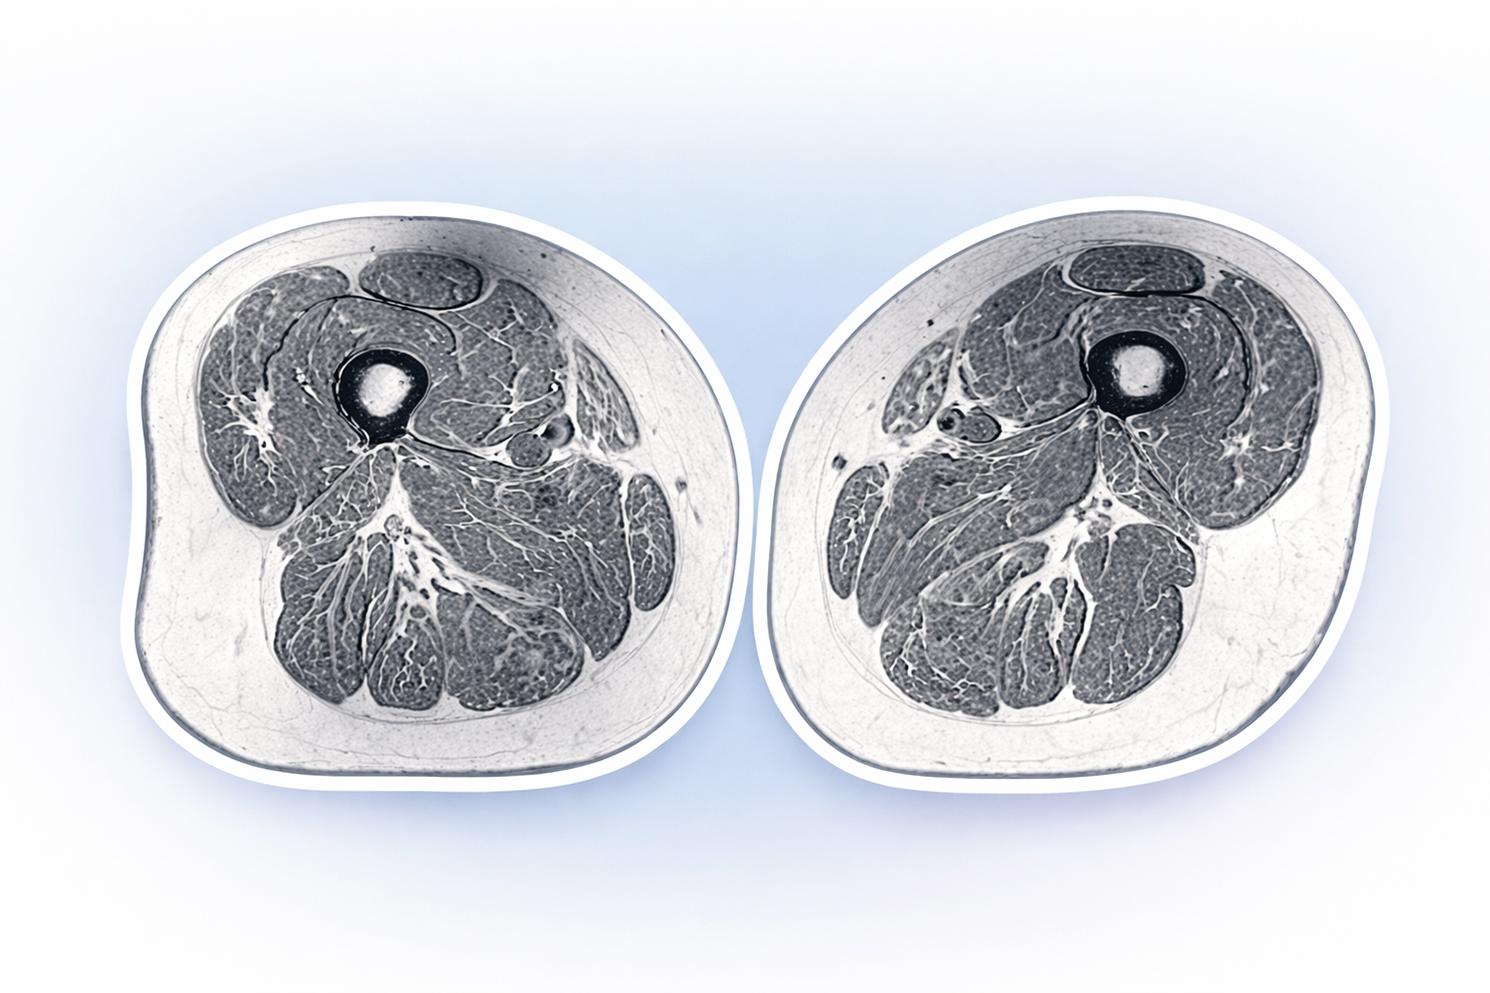

Изображение на МРТ-снимке бедра 62-летней женщины, которая в течение года 87% калорий получала из ультрапереработанных продуктов, выглядит как фото высококачественного стейка с ярко выраженной мраморной текстурой — обильными мелкозернистыми прожилками жира.

Прожилки жира, скрывающиеся между мышечными волокнами и внутри них, могут сигнализировать о серьезных проблемах со здоровьем, доктор Зехра Аккая из Калифорнийского университета в Сан-Франциско. Аккая — ведущий автор исследования, в котором анализировалось влияние ультрапереработанных продуктов на внутримышечный жир у людей, подверженных риску остеопороза коленного сустава.

Исследователи обнаружили, что чем больше ультрапереработанных продуктов потребляли люди, тем больше внутримышечного жира у них было в мышцах бедер, причем независимо от калорийности рациона и уровня физической активности. На МРТ можно увидеть, как жировую дегенерацию мышц, при которой полосы жира замещают мышечные волокна.